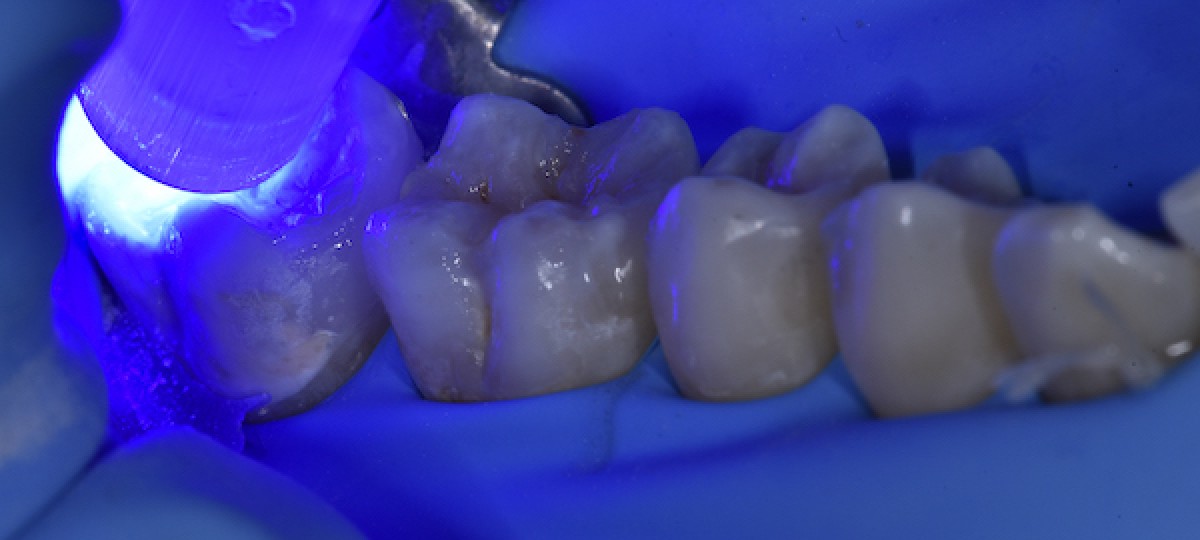

Selective enamel etching (37% orthophosphoric acid) for 30” on enamel. Etching was performed in two separate steps for better timing control (Fig. 7)